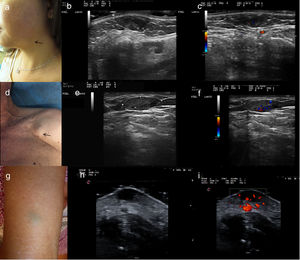

a) Caso 1: presentación clínica en forma de nódulo subcutáneo de 10mm diámetro con superficie azulada, localizado en la región mandibular izquierda. b) Examen ecográfico en modo B. Lesión hipoecoica bien definida, homogénea localizada en dermis con puntos hiperecoicos sin sombre acústica posterior. c) Examen ecográfico modo Doppler color. Mínimas áreas vasculares localizadas en el interior de la lesión. d) Caso 2: presentación clínica en forma de masa subcutánea de 20mm de diámetro, sin alteraciones epidérmicas, localizada en región pectoral derecha. e) Examen ecográfico modo Doppler color. Lesión hipoecoica, homogénea, bien delimitada, localizada en tejido celular subcutáneo. f) Examen ecográfico modo Doppler color. Vascularización moderada en el interior de la lesión. g) Caso 3: presentación clínica. Lesión subcutánea de 1cm de diámetro con la epidermis suprayacente ligeramente verde-azulada. h) Examen ecográfico en modo B. Lesión hipoecoica localizada en dermis, bien delimitada. i) Examen ecográfico modo Doppler color. Vascularización intralesional y perilesional prominente.

El primer caso era una mujer de 49 años, que consultó por una lesión asintomática localizada en rama mandibular izquierda de 2 años de evolución. En la exploración, presentaba un nódulo localizado en partes blandas, de 1cm de diámetro, con la epidermis suprayacente ligeramente azulada, y de consistencia elástica (fig. 1a). Se realizó una ecografía (Esaote MyLab 18MHz), observándose en modo B una lesión hipoecoica localizada en dermis, bien delimitada, con áreas anecoicas en su interior y puntos hiperecogénicos intralesionales sin sombra acústica posterior, con leve vascularización intralesional en el modo Doppler color (fig. 1b y c). Histológicamente, se observaron canales vasculares dilatados interconectados con paredes finas y estructuras seudopapilares en el interior. Además, presentaba áreas de calcificaciones y trombos vasculares recanalizados (fig. 2a y b).

El segundo caso era un varón de 72 años, en seguimiento por cáncer cutáneo no melanoma en la región facial y el tronco, que consultó por una lesión asintomática en región pectoral izquierda de más de 6 meses de evolución. En la exploración presentaba una lesión localizada en partes blandas, de 2cm de diámetro, sin alteraciones epidérmicas asociadas, de consistencia elástica y fácilmente desplazable (fig. 1d). Mediante ecografía cutánea (Esaote MyLab 18MHz) se visualizó una lesión hipoecogénica localizada en tejido subcutáneo, bien delimitada, con presencia de vascularización intralesional en modo Doppler color (fig. 1e y f). El estudio histológico evidenció canales vasculares más dilatados que el caso anterior, sin áreas de calcificaciones ni trombos significativos (fig. 2c).

El tercer caso era una mujer de 77 años, sin antecedentes de interés, que consultó por una lesión asintomática localizada en la cara externa del brazo derecho de años de evolución, de lento crecimiento. En la exploración presentaba una lesión subcutánea de 1cm de diámetro, de consistencia elástica y con la epidermis suprayacente ligeramente verde-azulada (fig. 1g). Se realizó una ecografía cutánea (Esaote MyLab 18MHz), visualizándose una lesión de ecogenicidad mixta con áreas anecoicas e hipoecoicas, localizada en la dermis, bien delimitada, con vascularización intralesional y perilesional prominente en el modo Doppler color (fig. 1h e i). El estudio histológico evidenció canales vasculares dilatados interconectados entre sí, formando un patrón sinusoidal, sin observarse calcificaciones ni trombos (fig. 2d).